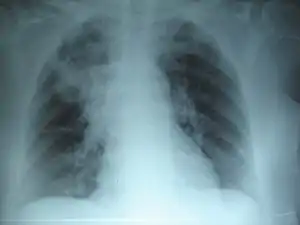

![]() На рентгенограмі характерні фіброзні зміни На рентгенограмі характерні фіброзні зміни | |

Бронхо-легенева форма муковісцидозу проявляється повторними і затяжними бронхітами, двобічними вогнищевими пневмоніями, наслідком яких є розвиток ателектазів, бронхоетказів і пневмосклерозу. Відмічається постійна віддишка і ціаноз. Грудна клітка бочкоподібна, нігтьові фаланги мають форму барабанних паличок. Хронічна гіпертензія малого кола кровообігу, зумовлена хронічним запальним процесом у легенях, веде до формування легеневого серця та серцевої недостатності. Часто виникають ателектази з розвитком хронічної пневмонії та бронхоектазів.